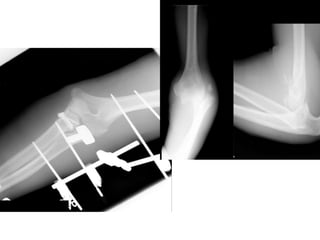

32-year-old male, fell from roof

• Left elbow injury

• Neurovascular

structure intact

• Closed injury

• Moderate

swelling

CT scan

Approach

• Fix the coronoid? What technique?

• Radial head fix or replace?

• How do you repair collateral ligaments:

– Drill holes or suture anchors

• What are the sequence of events for

treatment

• Posterior approach

• Pieced together radial head on

back table

• Suture anchor in coronoid base

• Fix head to plate

• Weave sutures through LCL

• Run sutures in capsule over

coronoid

32-year-old male, fellfrom roof • Left elbow injury • Neurovascular structure intact • Closed injury • Moderate swelling

Approach • Fix thecoronoid? What technique? • Radial head fix or replace? • How do you repair collateral ligaments: – Drill holes or suture anchors • What are the sequence of events for treatment

Treatment • Posterior approach •Pieced together radial head on back table • Suture anchor in coronoid base • Fix head to plate • Weave sutures through LCL • Run sutures in capsule over coronoid